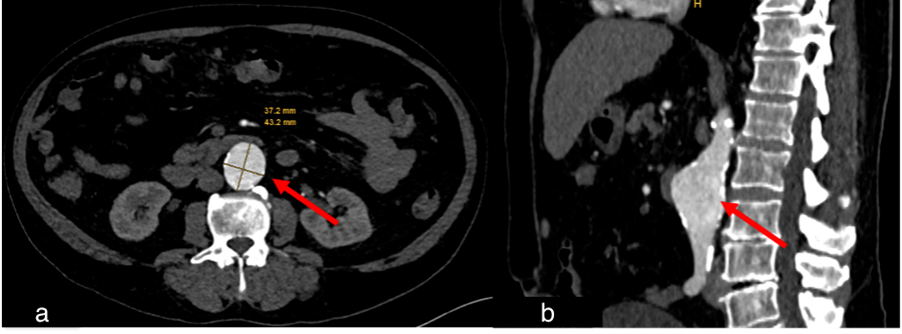

Figure 6.

Case 3, 76-year-old male. Initial chest and abdominal CT to investigate potential infections, including COVID-19 findings, revealed no infectious source. However, there was strong suspicion for metastasized carcinoma: (a) Wall thickening of a urachal remnant raised concern for urachal carcinoma with infiltration of theabdominal wall (red arrow). (b) Enlarged lymph nodes were suspicious for lymph node metastases (red arrow). (c) A peritoneal soft tissue mass suggested peritoneal metastasis (red arrow). (d) A solid pulmonary nodule in the lung raised concern for lung metastases (red arrow). (e) Multiple sclerotic lesions in the spine were indicative of osseous metastasis (red arrow). Histopathological examination following surgical intervention confirmed the diagnosis of metastasized sigmoid carcinoma.